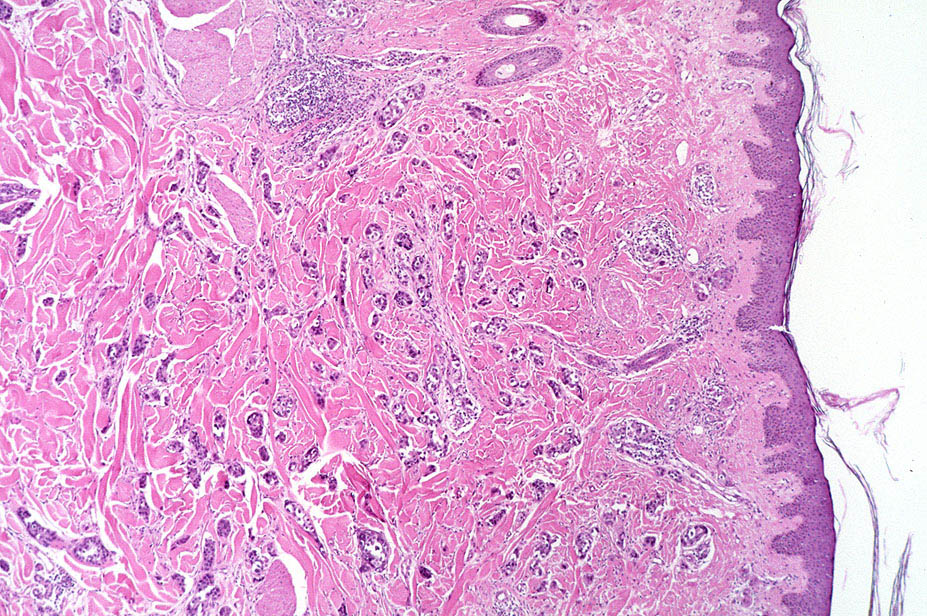

Breast cancer = سرطان الثدي